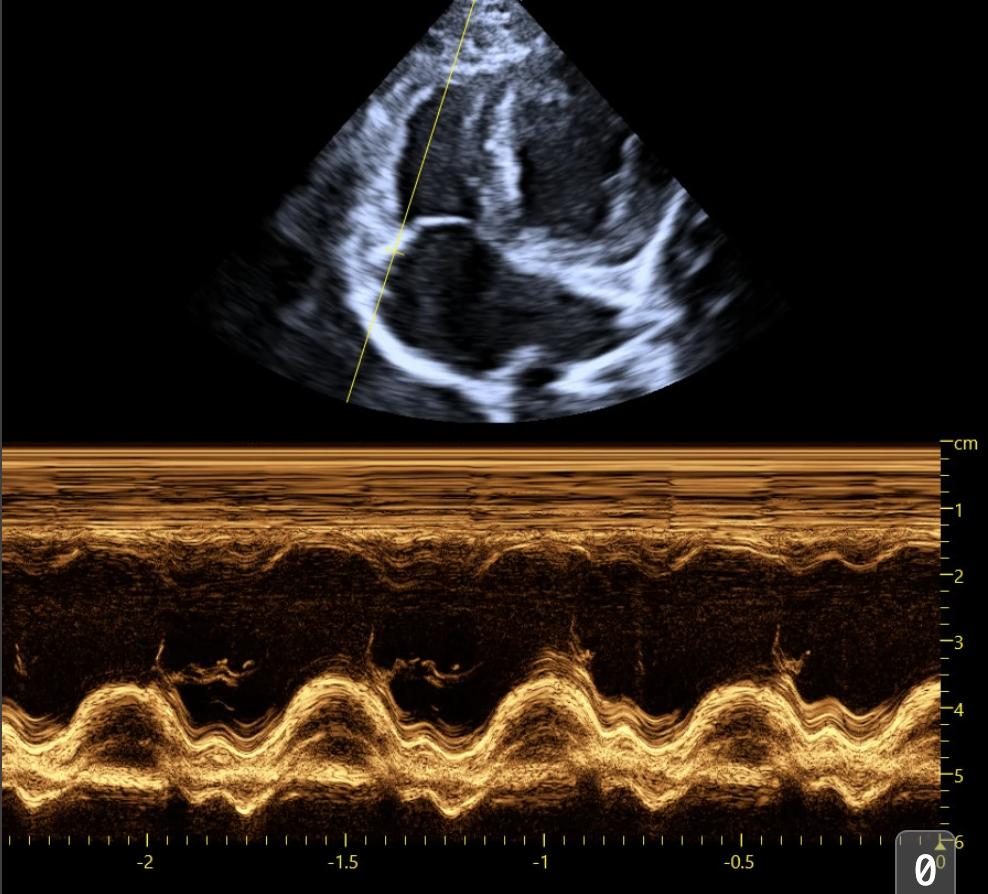

Drawing on our in-house research, training and echocardiography expertise, we can collaborate with current and planned research trials to advise on protocol design, deliver training to sonographers to improve standardisation and reduce inter-operator variability, and perform analysis on canine and feline chamber dimensions, wall thickness, systolic and diastolic function, Doppler parameters, as well as global longitudinal strain analysis.

Our focus is on reproducibility and accuracy, so that you can observe treatment effects sooner, finding genuine changes above the 'noise' of measurement error and inter-observer variability. We utilise our neural networks to aid in detecting potential errors, and standardising measurements.